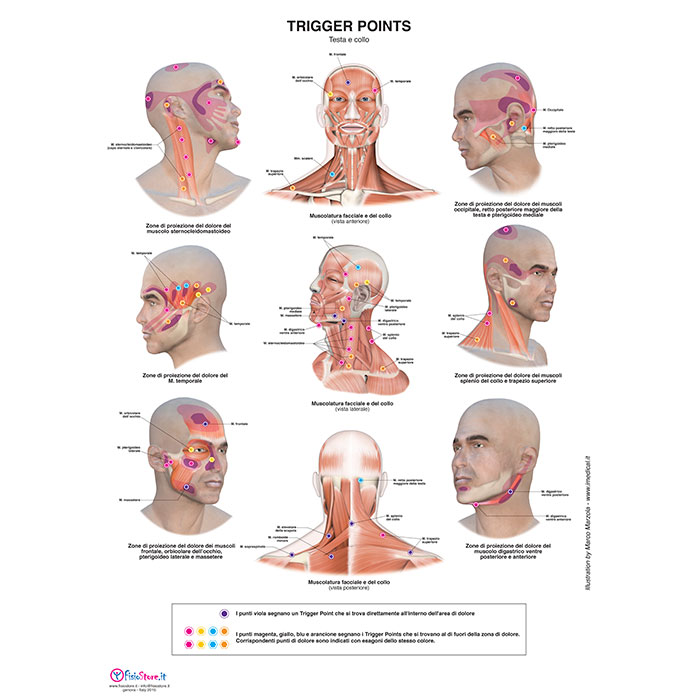

Visualizza Poster trigger points testa e collo di tendenza